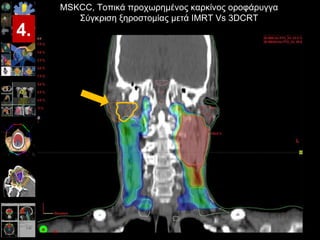

Proportion (%) IMRT 3DCRT 3 DCRT IMRT Acute Late Grade    1 Grade > 1 P < 0.001 Συχνότητα ξηροστομίας μετά από >12 μήνες παρακολούθηση (IMRT = 29pts / 3DCRT = 55pts) MSKCC,  Τοπικά προχωρημένος καρκίνος οροφάρυγγα Σύγκριση ξηροστομίας μετά  IMRT Vs 3DCRT Lee et al ,  IJROBP, Nov 15, 2006 4. 34 35 65 33 67 76 24 66

Proportion (%) IMRT3DCRT 3 DCRT IMRT Acute Late Grade  1 Grade > 1 P < 0.001 Συχνότητα ξηροστομίας μετά από >12 μήνες παρακολούθηση (IMRT = 29pts / 3DCRT = 55pts) MSKCC, Τοπικά προχωρημένος καρκίνος οροφάρυγγα Σύγκριση ξηροστομίας μετά IMRT Vs 3DCRT Lee et al , IJROBP, Nov 15, 2006 4. 34 35 65 33 67 76 24 66